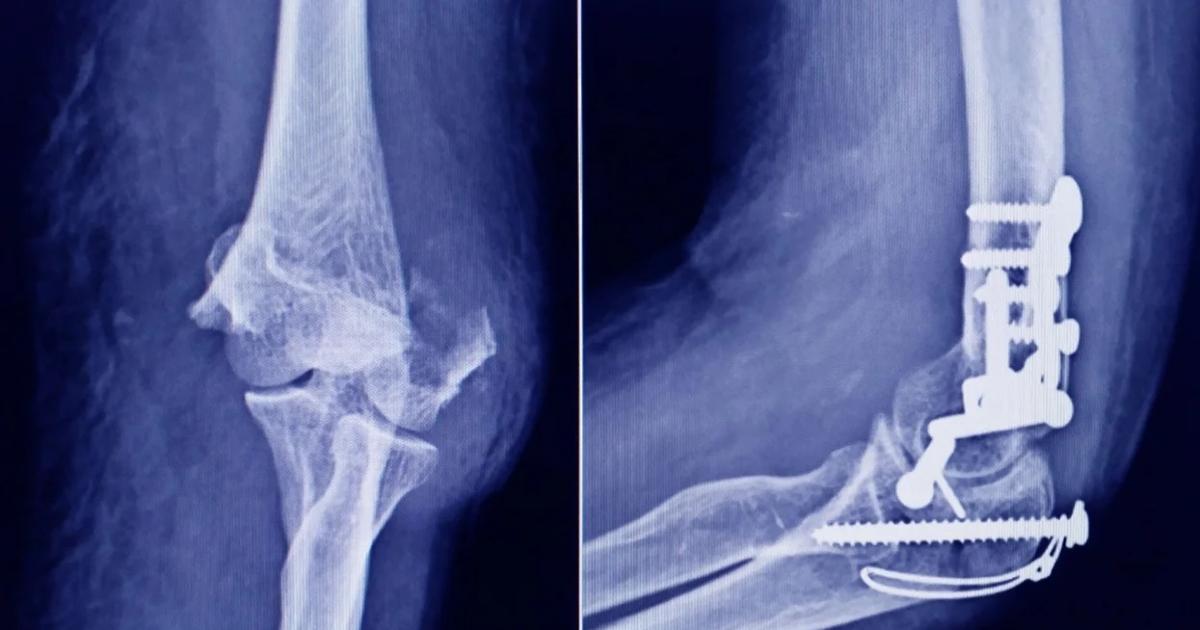

La Anmat advirtió a la población por un tornillo utilizado en cirugías traumatológicas debido a que es falso, por lo que su uso representa riesgo para la salud del paciente al que se lo implante

Se trata de un tornillo utilizado en cirugías traumatológicas que fue detectado durante una inspección de control de mercado realizada en una ortopedia ubicada en la ciudad de San Miguel de Tucumán.

Dicho tornillo es producido por la firma Stryker Corporation, que se encuentra registrada ante ANMAT bajo el PM 594-139. Luego de la inspección, se exhibió la muestra recolectada ante la responsable técnica de dicha empresa, quien afirmó que se trataba de un producto falsificado.

Las autoridades de la Anmat dieron a conocer las características del producto para su advertencia: STRYKER 10 mm X 28 mm - BIOABSORBABLE - ACL INTERFERENCE SCREW - REF 234-010-067 - LOT 90905.